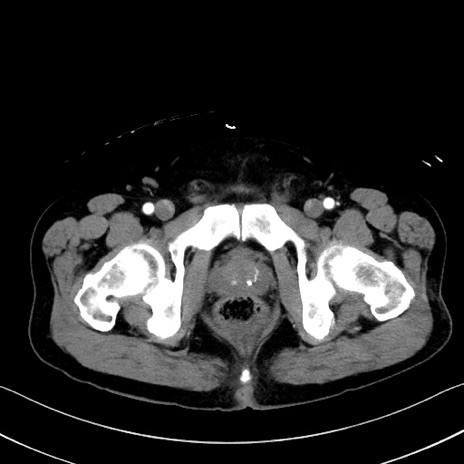

冠状断像